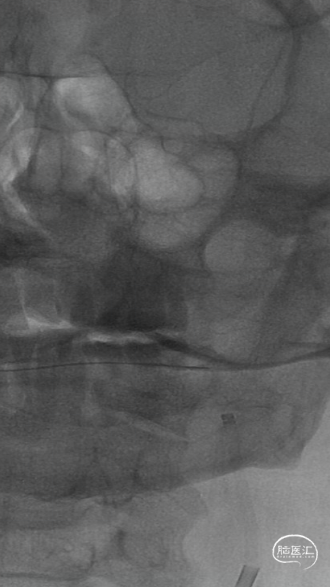

微导管越过大脑中动脉血栓后,以4-20mm Solitaire AB支架,配合6F 115cm SKATHI远端通路导管取栓一次,复查造影大脑中动脉血栓通畅,远端仍有少许血栓,观察后血流能够维持。

回撤SKATHI远端通路导管至C3段,通过导管再次释放SPIDER保护伞,回撤导管至颈总动脉,造影见C1段严重狭窄,以4-30mm球囊扩张狭窄段,复查造影狭窄段好转,远端再次闭塞,考虑斑块或血栓脱落,立即置入7-40 wallstent支架。

复查造影远端仍然闭塞,负压状态上行SKATHI远端通路导管回收保护伞并抽吸血栓,可见保护伞及大量血栓取出,复查造影C3段仍有血栓。再次上行SKATHI远端通路导管抽吸取栓,复查造影示远端血流通畅。